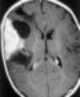

Desmoplastic infantile ganglioglioma